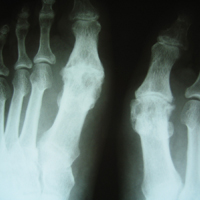

• Αρθρίτις μεταταρσιοφαλαγγικής